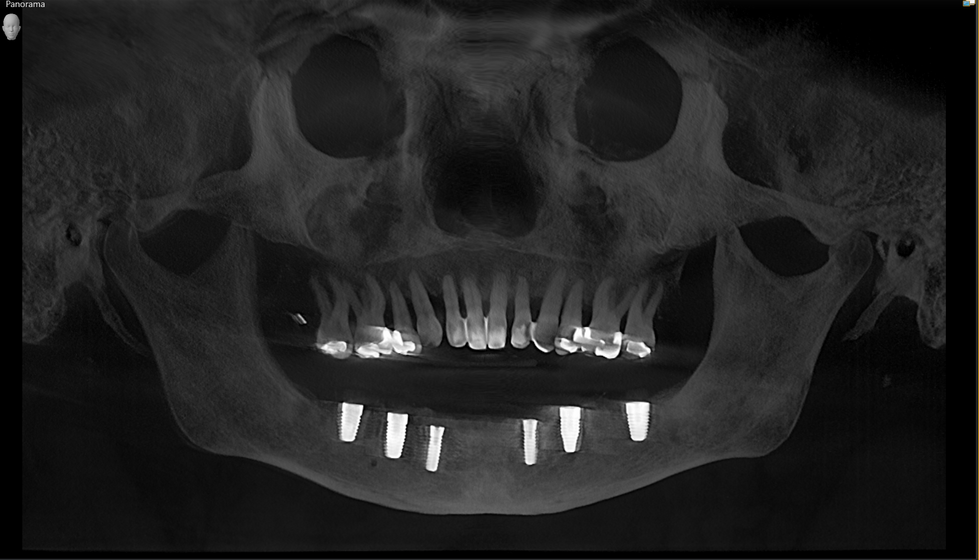

AOX W ceramic implants

AOX case full upper and lower

AOX upper and lower done with full ceramic screw retained implants w Yomi Robot guide.